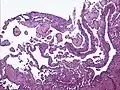

| Micrograph of a kaposiform hemangioendothelioma with "glomeruloid" nodules of endothelial cells. | |

- Kaposiform hemangioendothelioma (also known as "Infantile kaposiform hemangioendothelioma"[3]) is an uncommon vascular tumor, first described by Niedt, Greco, et al. (Hemangioma with Kaposi's sarcoma-like features: report of two cases.(Niedt GW, Greco MA, Wieczorek R, Blanc WA, Knowles DM 2nd. that affects infants and young children, with rare cases having also been reported in adults. Pediatr Pathol. 1989;9(5):567-75.)[2]: 596 [3]: 1782